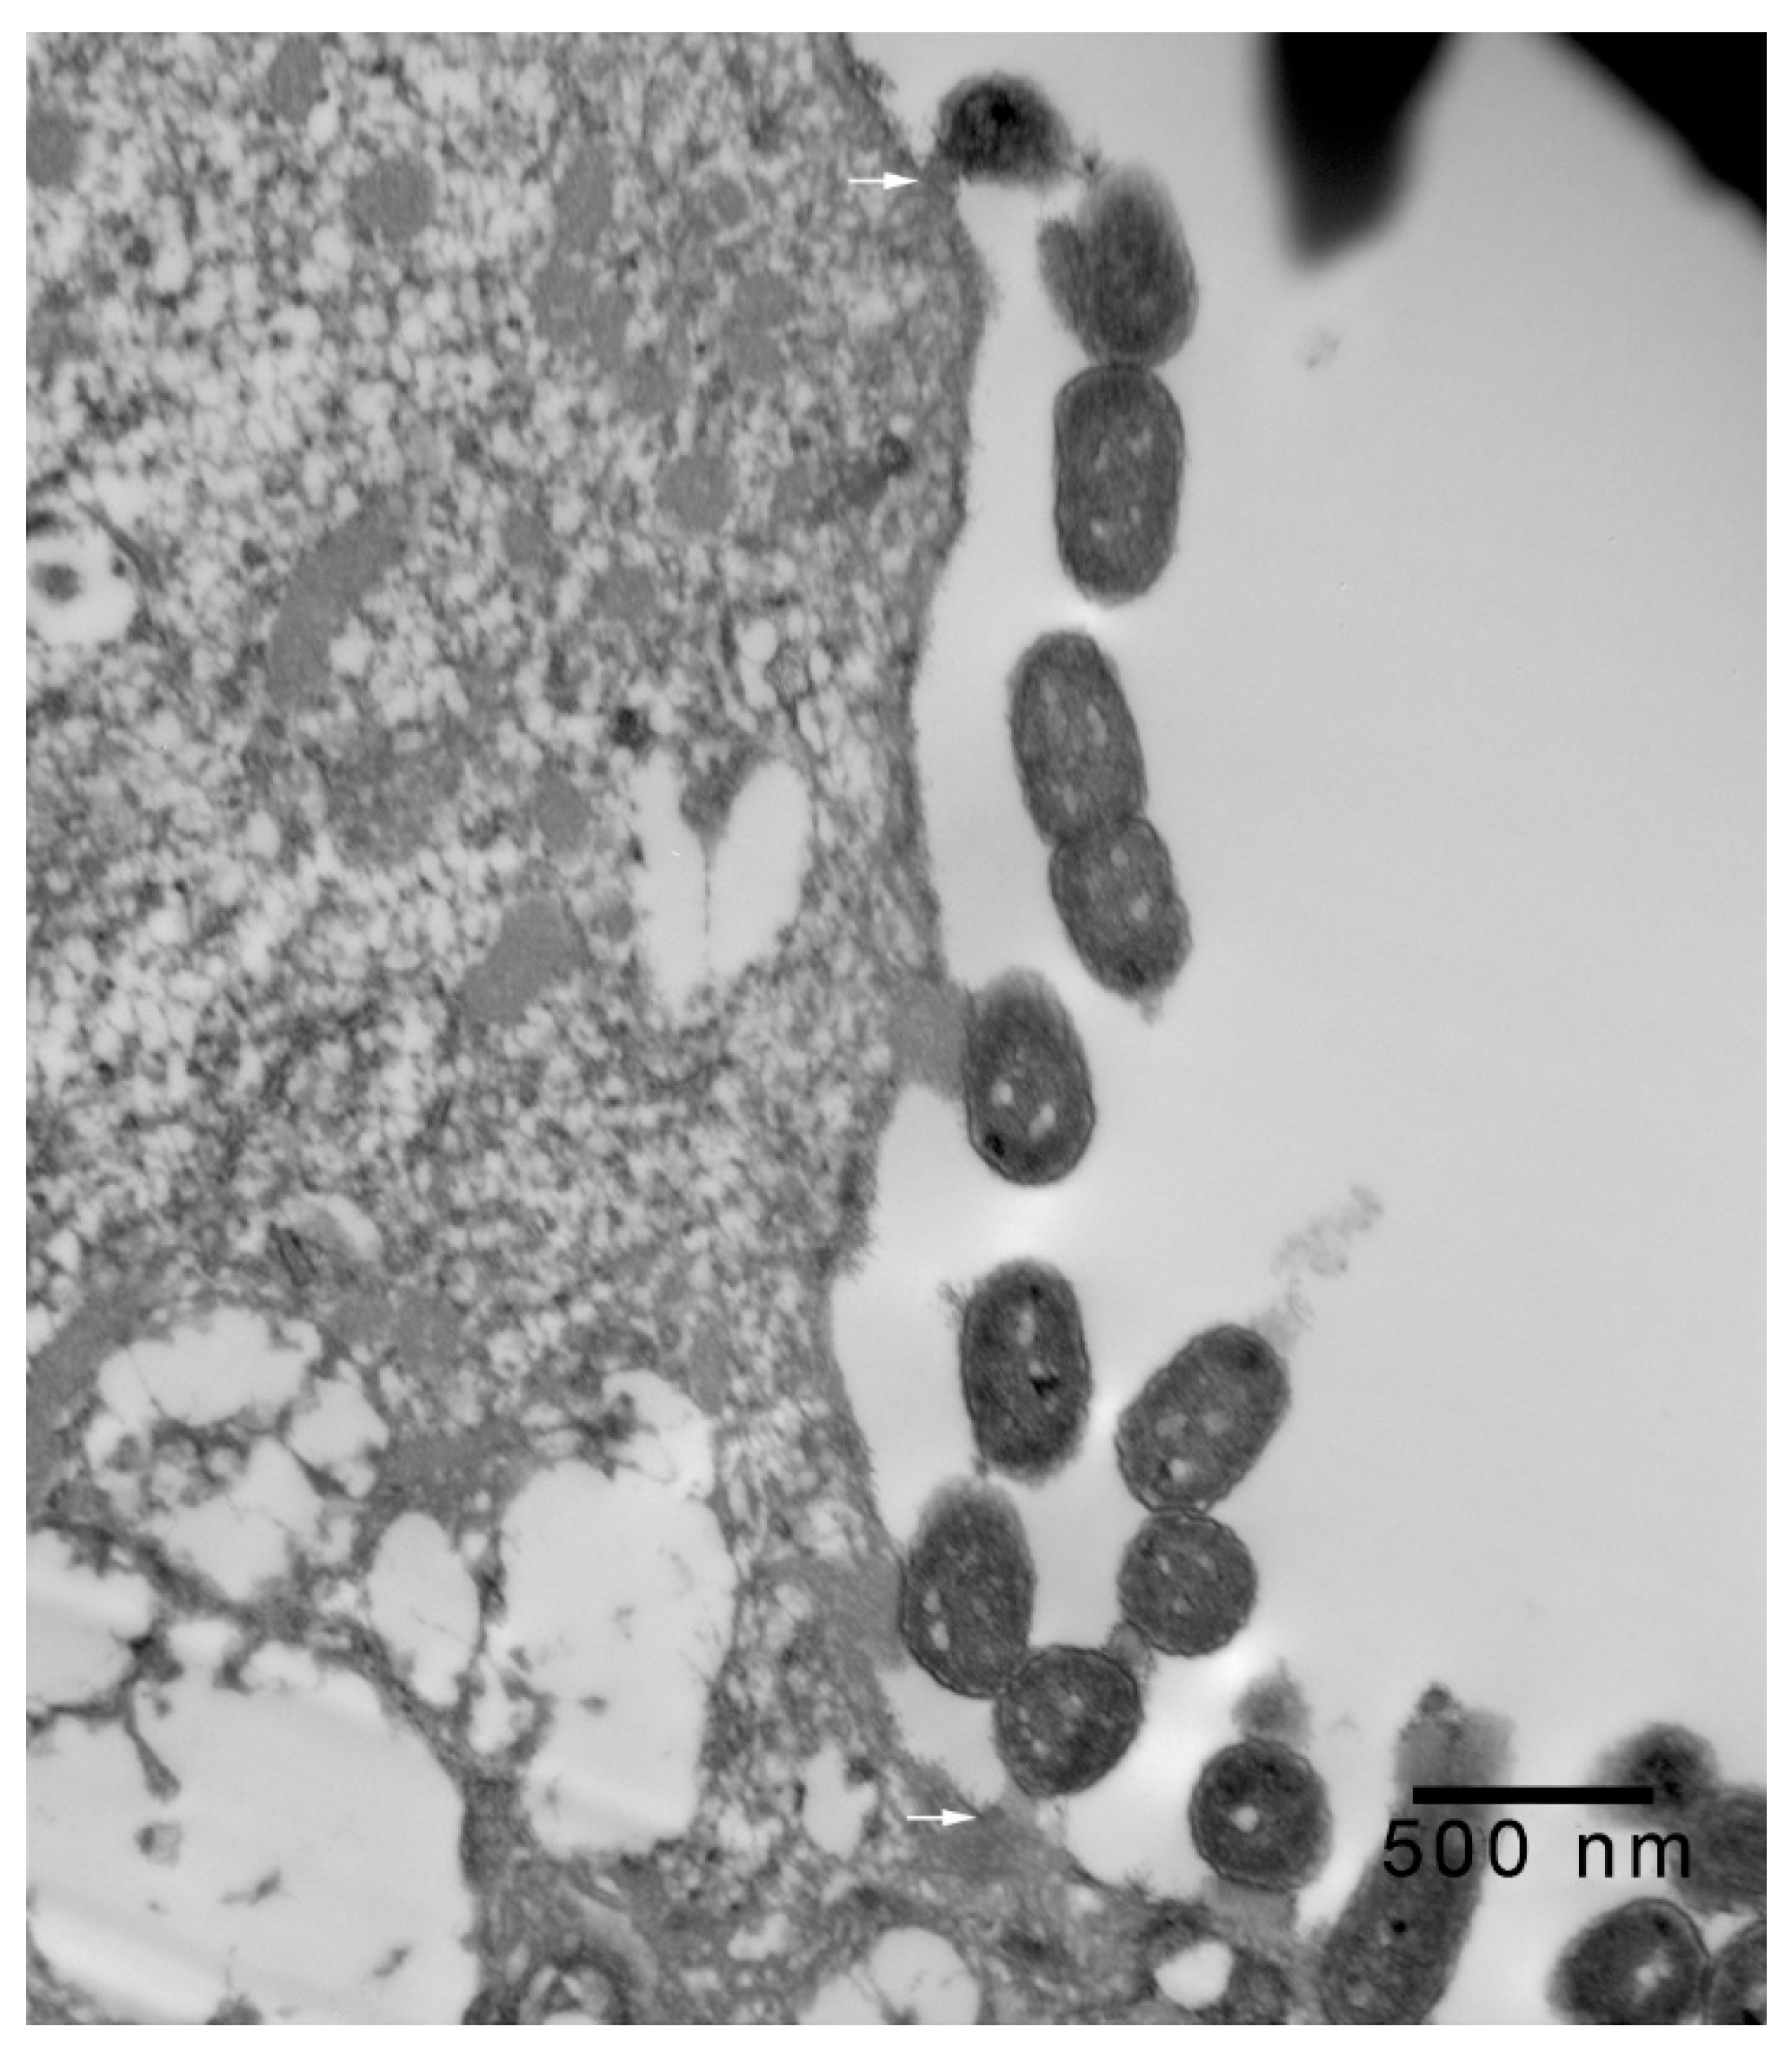

In 1-μm thick Araldite sections of urinary bladder prepared from tissues originally contained within the paraffin blocks [25], bacteria were detected only in piglet 15627 (Figure 1). In this piglet, in which bladder sections were oriented such that all three cell layers (basal, intermediate and superficial or umbrella) of the urothelium [26,27,28,29] were visible, bacteria, corresponding to bovine-origin strain 2891, were diffusely adherent to the apical surfaces of umbrella cells. By TEM, bacterial cells were found intimately attached to pedestals (Figure 2, Figure 3 and Figure 4). Some bacterial cells appeared to be attached to microplicae, preceding pedestal formation (Figure 4).

Figure 4.

Transmission electron photomicrograph of a thin section of a superficial epithelial (umbrella) cell of the urinary bladder of piglet 15627, 8 days PI with bovine-origin strain 2891. This field shows more extensive colonization, with bacteria attached to pedestals and apparent early attachment to microplicae (arrows). Bar = 500 nm.

Morphologically, the pedestals to which bacteria in the urinary bladder of piglet 15627 were intimately attached were consistent with actin pedestals induced by EHEC and enteropathogenic E. coli (EPEC) in intestinal epithelium [24]. To our knowledge, this is the first report of intimate bacterial adherence and actin pedestals in the uroepithelium in any species. Staley et al. [30] first reported these lesions in 1969, describing them as attachment and microvillous exfoliation in ileal enterocytes of newborn, cesarean-derived piglets intragastrically inoculated with an E. coli strain belonging to a classical EPEC serotype, O55:H7. Takeuchi et al. [31] later described these lesions as occurring in rabbits inoculated with RDEC-1, a rabbit-origin O15:NM E. coli later classified as an EPEC [23]. Soon thereafter, the lesions were recognized in human infants with EPEC infection [32,33]. Moon et al. coined the term “attaching and effacing” to describe intimate attachment and effacement of microvilli in the intestinal epithelium of piglets and rabbits by EPEC [23]. Knutton et al. [34] first determined that the electron-dense material underlying the bacteria within the pedestals was filamentous actin. Over the past 50 years since the initial report by Staley et al. [30], numerous studies, many at the molecular level, have elucidated key bacterial and host factors involved in the pathogenesis of intimate attachment and pedestal formation [29].